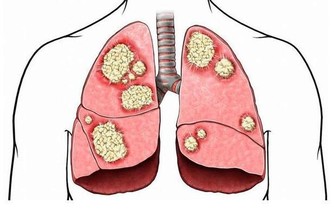

腫瘤科:少吃油炸食物

腫瘤不找你,你千萬別主動找它!特別是要避免吃過多的高脂、高鹽、高糖的食物。否則,你就是在人為地給自己誘發腫瘤!

小貼士:這些食物你遠離了嗎?

油炸食物:重複多次的油,更易產生致癌物。

燒烤:烤焦的肉和皮中易含有致癌物苯丙芘。

醃製食品:醃製過程中食物可能產生二甲基亞硝酸鹽,易導致消化道癌變。

霉變食品:被黴菌污染後會產生致癌物——黃曲霉菌素。

太麻、太辣、太燙的食物:是食道癌的誘發原因。